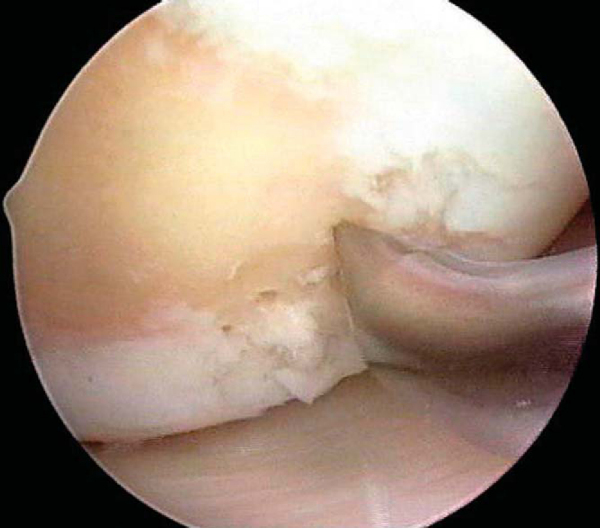

After careful assessment of the full-thickness articular cartilage lesion, we débride the exposed bone of all remaining unstable cartilage. We use a hand-held, curved curet and a full-radius resector to débride the cartilage. It is critical to débride all loose or marginally attached cartilage from the surrounding rim of the lesion (

Fig. 52-3

). Establishment of a stable full-thickness border of cartilage surrounding a central lesion is optimal for microfracture because it provides some degree of protection to the regenerating tissue that is forming in the treated lesion. The calcified cartilage layer that remains as a cap to many lesions must be removed, preferably by use of a curet (see

). Thorough and complete removal of the calcified cartilage layer is extremely important on the basis of animal studies we have completed. [1] [2] Care should be taken to maintain the integrity of the subchondral plate by not débriding too deeply; otherwise, the joint shape and geometry might be negatively altered. This prepared lesion, with a stable perpendicular edge of healthy, well-attached viable cartilage surrounding the defect, provides a pool that helps hold the marrow clot (“super clot,” as we have termed it) as it forms. [9] [11]